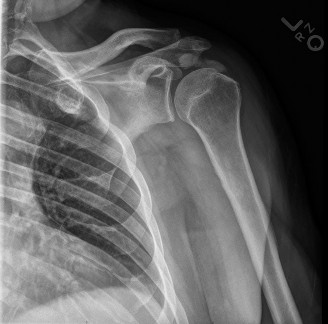

X-ray Findings

- Modality of Choice: Plain radiographs (AP, lateral, oblique views of the elbow) are the initial and often definitive diagnostic tool.

- Findings: They will demonstrate areas of radiodensity (calcification) within the soft tissues adjacent to the bone, specifically in the suspected tendon.

- Location: Crucial for correlating with clinical findings (e.g., triceps insertion on olecranon, common extensor/flexor origins on epicondyles).

- Size and Shape: Can vary from small, punctate deposits to large, amorphous collections.

- Morphology (Phases):

- Formative Phase: Typically well-defined, dense, homogeneous, and discrete calcifications.

- Resorptive Phase: Often ill-defined, fluffy, hazy, and amorphous, indicating active calcium resorption and inflammation. This phase correlates with acute, severe pain.

- Dynamic Imaging: Repeat radiographs over time can show progression, regression, or changes in morphology, correlating with the phases of the condition.

Figure 1: Plain radiograph demonstrating calcific deposits adjacent to the olecranon, consistent with triceps tendon calcific tendonitis.